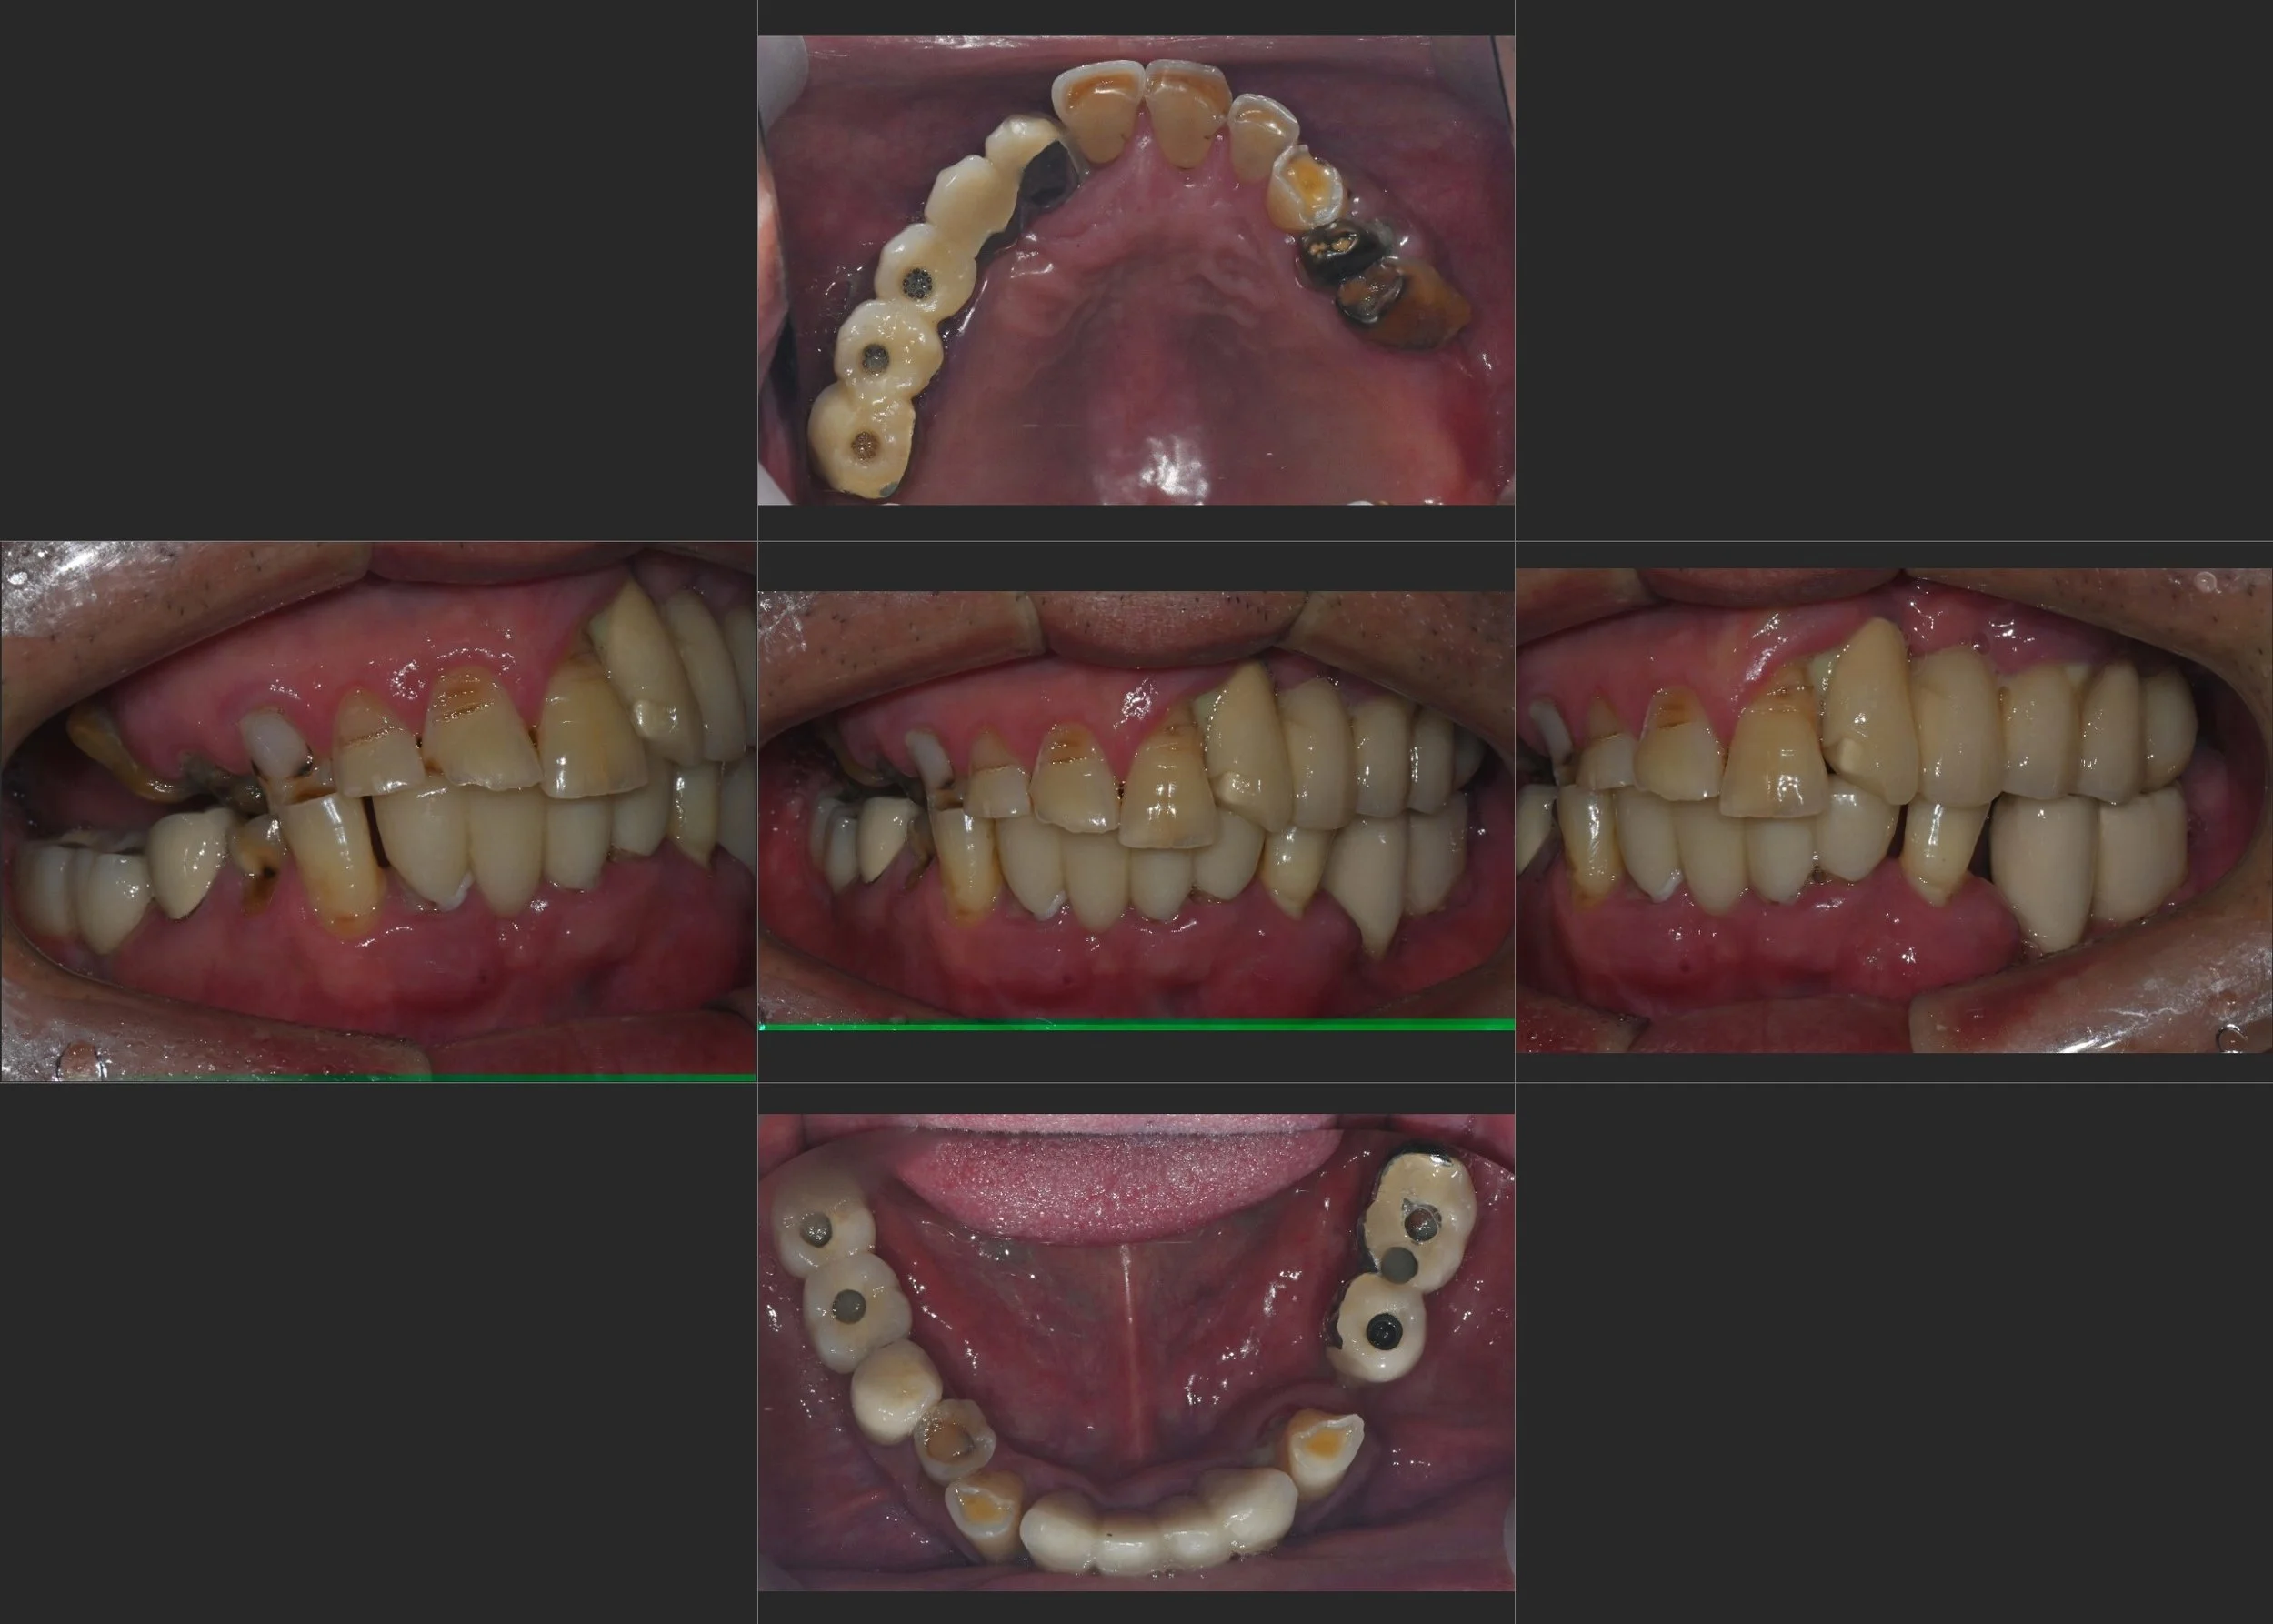

INTRA ORAL - BEFORE